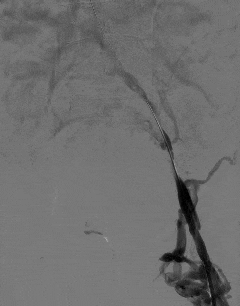

手术过程中,田轩团队凭借精湛的介入技术,经大隐静脉入路穿刺,成功开通闭塞的髂静脉。

术中造影进一步确认,李叔叔左下肢深静脉全程闭塞,血流无法正常回流。

团队随即采用球囊扩张导管逐级对闭塞血管进行精准扩张,逐步恢复血管管腔通畅性。

术后即时评估显示,左下肢髂静脉恢复部分血流,肢体回流障碍得到有效改善。

李叔叔术后即刻反馈,左下肢憋胀感明显减轻,肢体比术前轻松了许多。